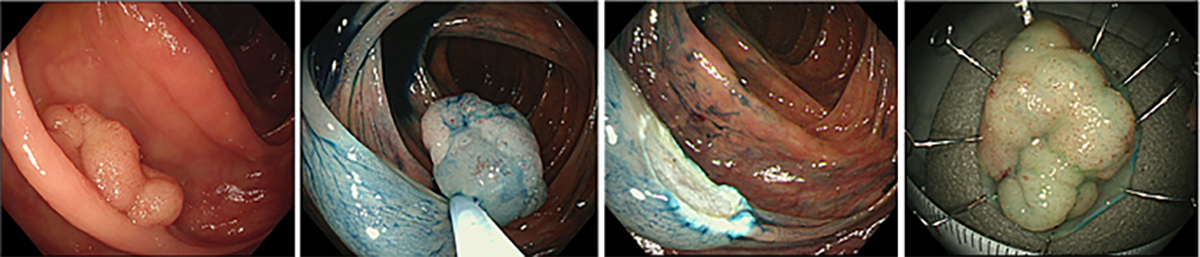

また、比較的大きなポリープや早期がんに対しては、短期入院のうえで内視鏡治療を行っています。一般的には、投げ輪状の電気メス(スネア)を用いて切除する内視鏡的粘膜切除術(EMR)が行われており(図2)、近年では病変を水中に浮かせて切除するUnderwater EMRも選択されるようになっています(図3)。